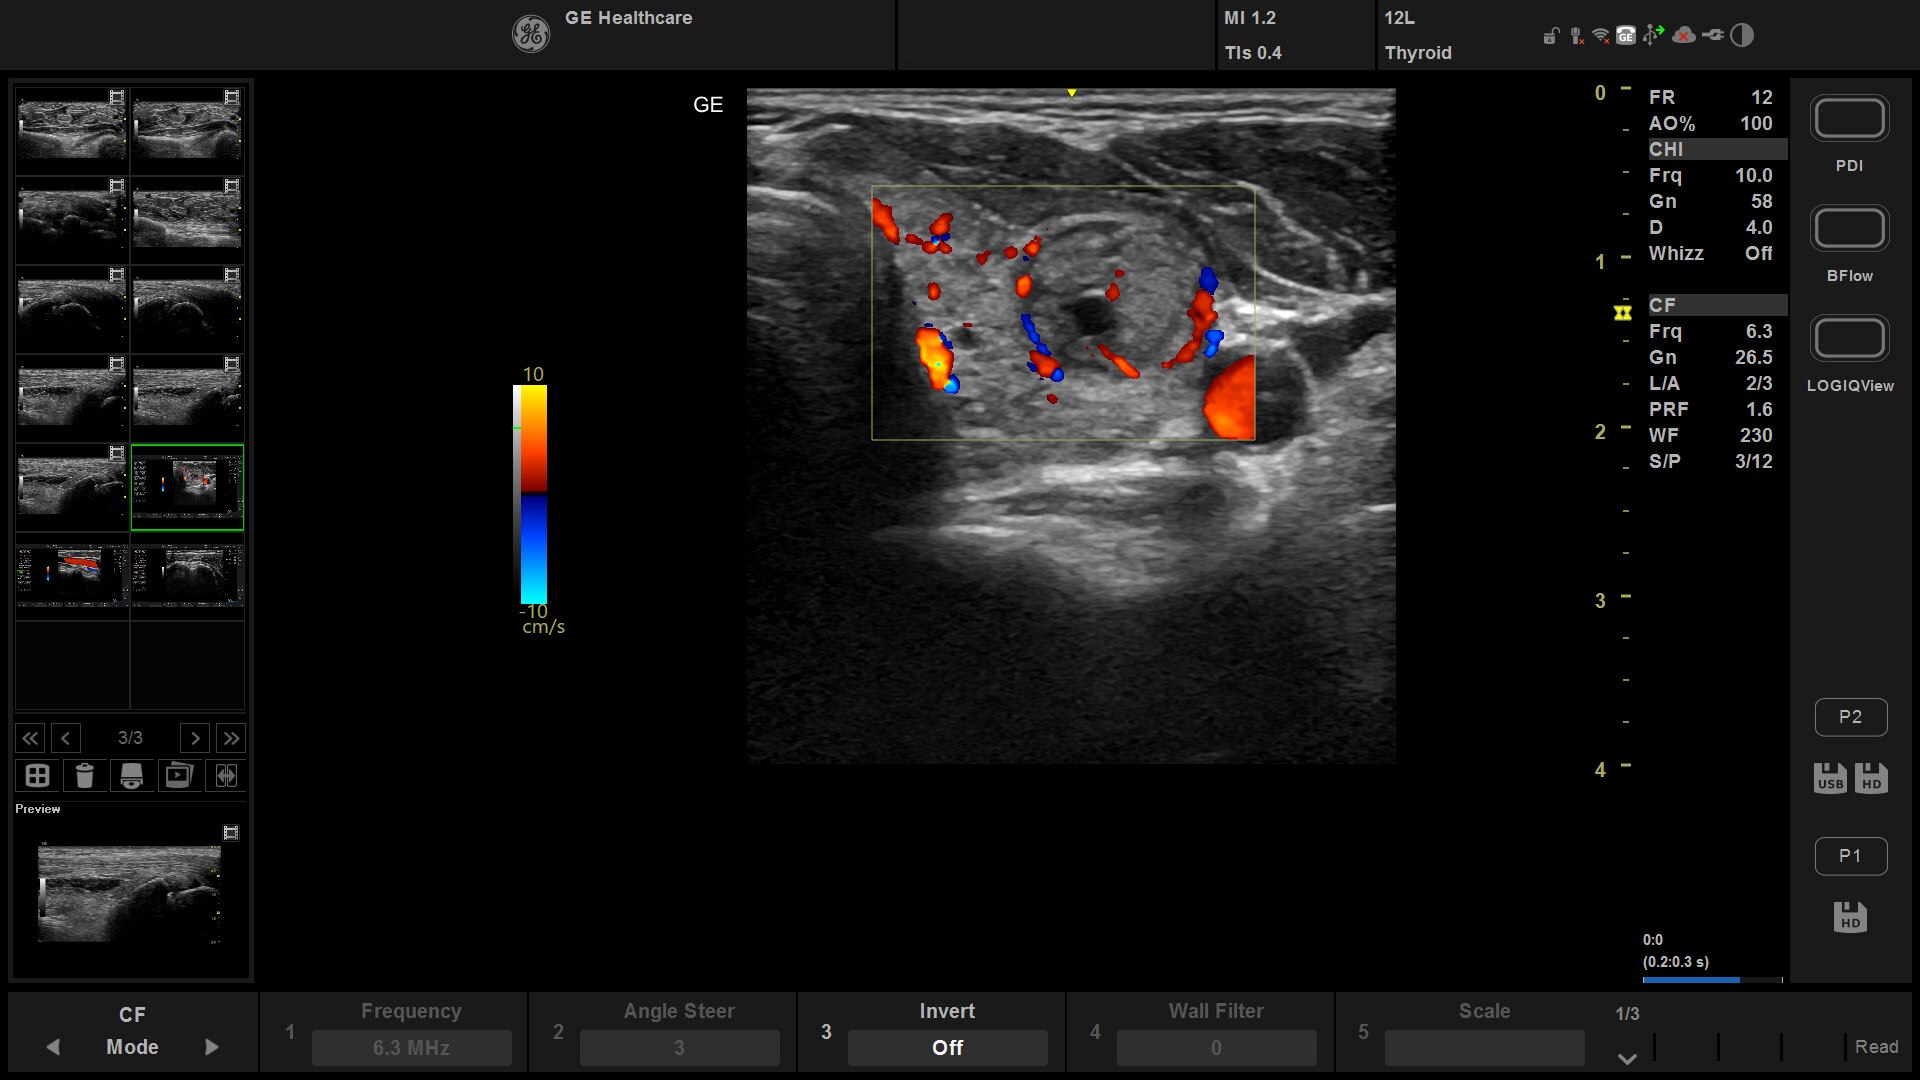

Suited for abdominal, small parts, cardiac, OB/GYN, vascular, and MSK exams

Versana Active delivers the imaging capability of a console in a hand-carried, lightweight package that enables you to actively take your system to your patients, on premises, or remote facilities. The reliable system brings the agility of a laptop unit with the capability for attaching to a cart. Adaptable to cover a broad range of everyday exams, it is easy to carry to clinics, offices, and beyond.

Versana Active features a wide range of advanced clinical applications and automated tools that simplify exams, streamline workflow, and enable fast, high-volume scanning to help you diagnose a wide spectrum of patient conditions.